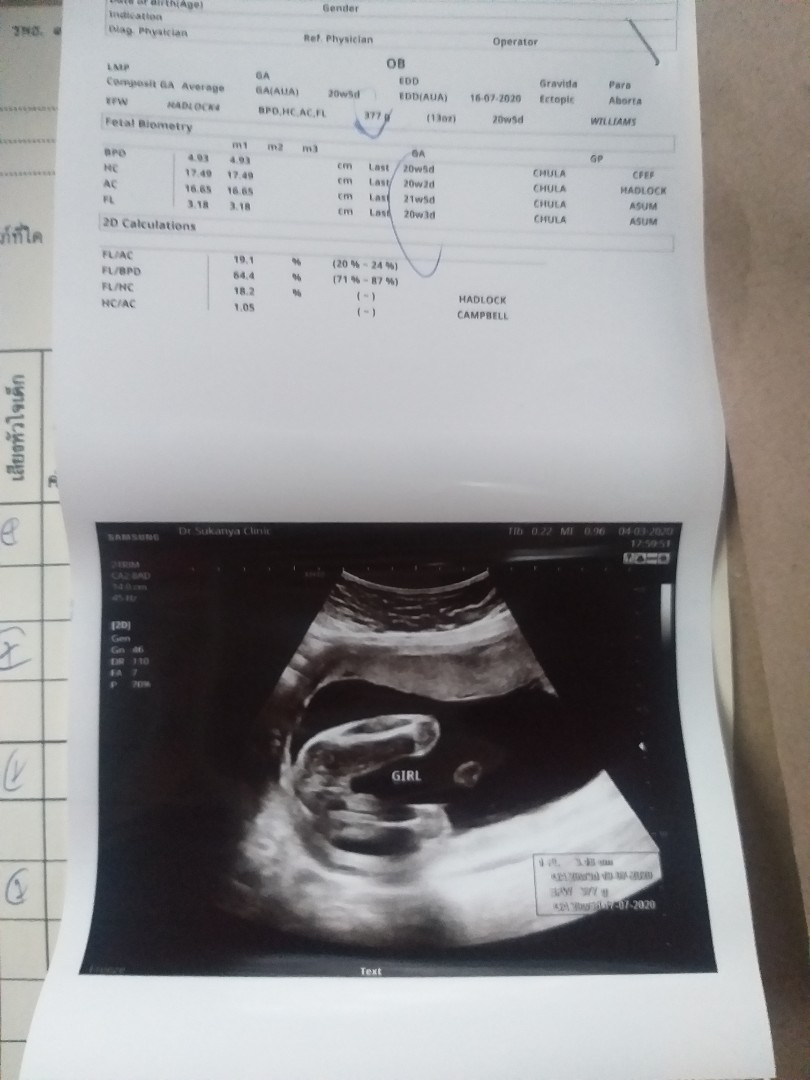

เพศลูก

อยากได้ผช ค่ะมีโอกาศไหมค่ะ มีคัยเคยซาวแบบนี้แต่ได้ผช ไหมค่ะ คุณหมอบอก ญ 70-80% ค่ะ

อันนี้หมอบอก100%เลยค่ะ😂😂😂😂

ดูจากรูป ได้ผู้หญิงนะคะ

บ้านนี้ก็หญิง 100% เลยจร้า

ดูแล้วน่าจะสาวน้อยนะคะ

น่าจะลูกสาวนะคะ

ลูกสาวค่ะแม่

น่าจะผญนะคะ

น่าจะญค่ะ

ผญ ค่ะ